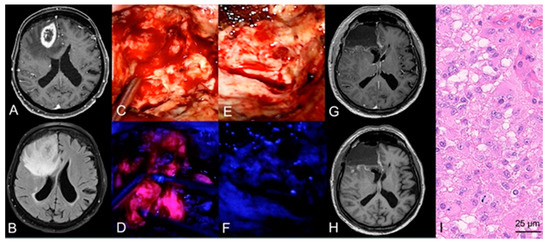

In the case of resection, 5-ALA fluorescence-guided surgery was conducted in 163 (90%) cases. Of these 163 cases, 5-ALA was able to detect tumor tissue during surgery by visible fluorescence in 161 (99%) cases. In detail, strong 5-ALA fluorescence was found as maximal fluorescence level in 153 (94%) cases, vague fluorescence in eight (5%), and no visible fluorescence in two (1%) cases. At the end of resection, a complete removal of visible fluorescence was achieved in 50 (31%) cases and in 111 (68%) cases residual fluorescence was present. In the remaining two cases, no information on residual fluorescence at the end of surgery was available. An illustrative case is provided in Figure 2.

Figure 2. Case illustration of a fluorescence-guided resection of a GBM. (A) Preoperative MRI demonstrates a lesion in the right frontal lobe with ring-like contrast-enhancement on T1-weighted sequences and hyperintensity on (B) FLAIR sequences in a 72-year-old male patient. (C) During tumor resection under white-light microscopy, (D) the neurosurgeon repeatedly switches to violet-blue excitation light to visualize tumor tissue with assistance of visible 5-ALA fluorescence. (E) At the end of surgery, the performing neurosurgeon investigates the resection cavity for potential residual tumor tissue and (F) does not detect any residual 5-ALA visible fluorescence. (G,H) After resection of the tumor, postoperative MRI including T1-weighted sequences with and without contrast-media show a complete resection of the contrast-enhancing tumor. (I) Histopathological analysis reveals a glioblastoma WHO grade IV.